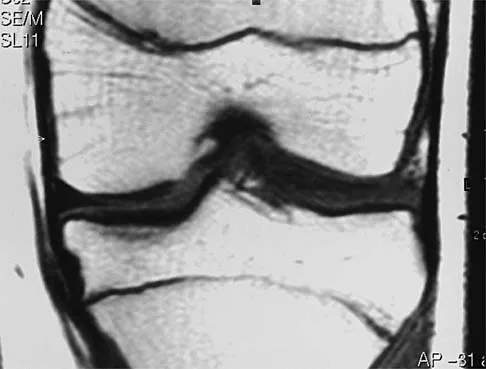

A 45-year-old male karate instructor sustained the injury shown in Figures 40a through 40c while practicing karate. The decision to proceed with surgery depends on which of the following factors?

Explanation

The most important criteria in determining the need for surgery following a nondisplaced or minimally displaced tibial plateau fracture is knee stability to varus/valgus stress. Soft-tissue injury noted on MRI may be addressed at a later time following fracture healing. This fracture pattern is amenable to nonsurgical management. Decisions regarding surgical intervention may be made up to 2 weeks after injury.